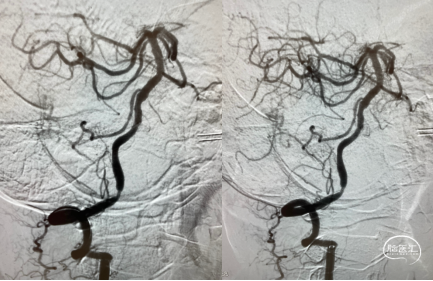

脑血管造影示左侧椎动脉颅内段闭塞,右侧椎动脉V1段起始部迂曲,远端V4段重度狭窄。

将6F通桥银蛇®DA远端通路导引导管(已连接Y阀、三通及肝素生理盐水装置)、泥鳅导丝同轴,沿鞘送入。在路径图指导下,在泥鳅导丝的引导下将银蛇®DA前端置于右侧椎动脉V2段以远,造影显示右侧椎动脉V4段狭窄,狭窄率约80%。